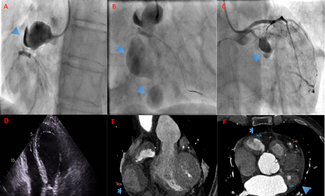

A 60-year-old male presented to the emergency department of our hospital with persistent dull pain in the lower and middle sternum with generalized sweating after a heated argument with another person, and his symptoms did not resolve after 3...